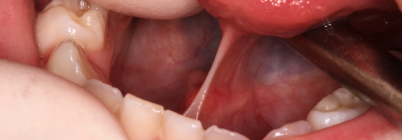

For the ‘Abcesses’ library we have created a simple PowerPoint presentation which includes a description of each image. If you find the PowerPoint version useful, please let us know via our contact form.

Download Abscesses PPT – 7 slides.